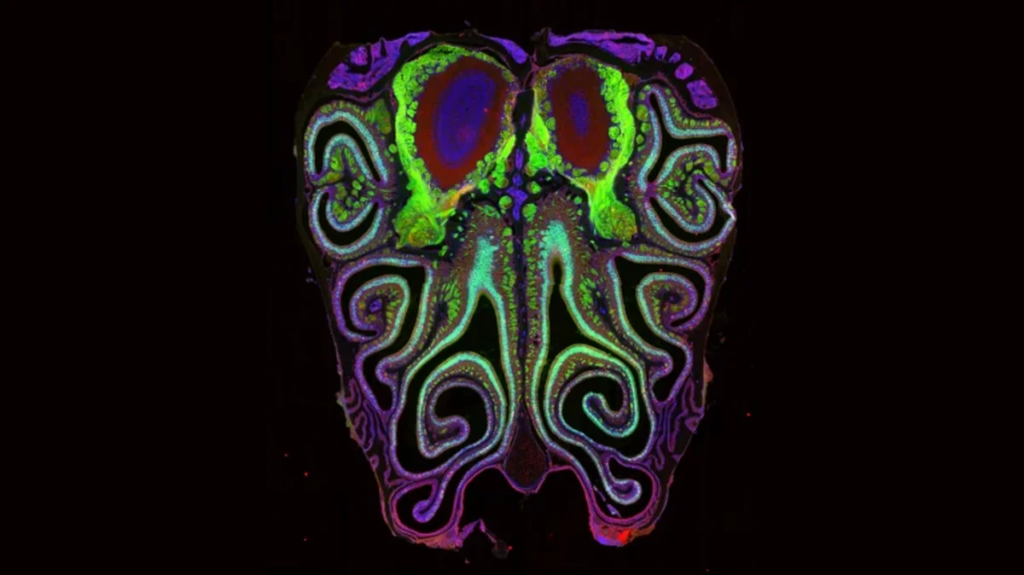

Uzun yıllardır biyoloji ders kitaplarında anlatılan koku alma sistemi modeli, yeni araştırmalarla ciddi biçimde sorgulanmaya başladı. Bilim insanları, burundaki koku alıcılarının işleyişinin sanılandan çok daha karmaşık olduğunu ortaya koydu.

Son çalışmalar ise bu sistemin daha dinamik olduğunu gösteriyor. Araştırmacılara göre koku reseptörleri yalnızca tek bir moleküle tepki vermekle kalmıyor; aynı zamanda farklı kimyasal bileşimleri birlikte değerlendirerek daha karmaşık bir algı oluşturuyor.

Bu durum, koku algısının sabit bir “eşleşme sistemi”nden ziyade, çoklu sinyallerin birleştiği esnek bir ağ gibi çalıştığını ortaya koyuyor.

🧠 Beyin ve Koku İlişkisi Daha Karmaşık

Yeni model, beynin kokuları yalnızca pasif şekilde “okumadığını”, aksine aktif biçimde yorumladığını gösteriyor. Bu da neden bazı kokuların kişiden kişiye farklı algılandığını ya da zamanla değişebildiğini açıklamaya yardımcı olabilir.